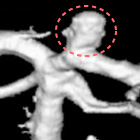

カテーテルと呼ばれるやわらかく細いチューブを腕や脚の付け根の血管から挿入し、X線透視画像を見ながら目的の血管までカテーテルを進め、カテーテルの先端から造影剤を注入して撮影することで、様々な方向から血管の形態を見る検査です。

血管を三次元的に表示させて、動脈瘤の複雑な形や、狭くなってしまった血管などを詳細に観察することもできます。

カテーテルからは造影剤のほかにも、コイルやステント、バルーンといった器具を挿入できるため、血管撮影で見つかった異常に対して血管内治療を行うことも可能です。